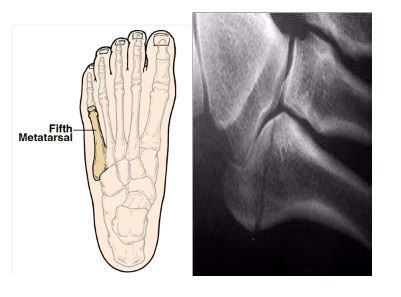

Discharge advice following attendance with a foot (metatarsal) fracture:

- You have fractured a bone in your foot